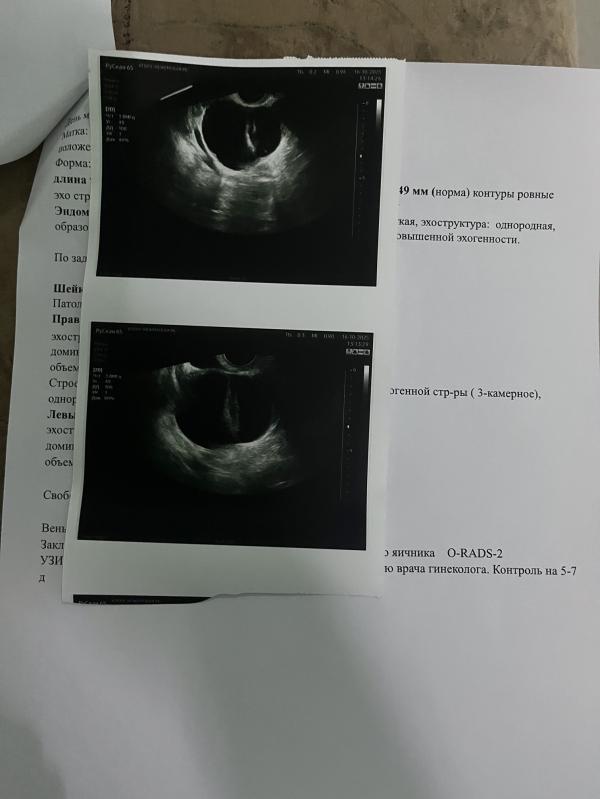

У меня была 3-х камерная киста на яичнике, но меньше размером, прям небольшая, сдавала анализы на онко, ходила на консультацию к онкологу, отправляли на мрт омт, но туда я не дошла, анализы все в норме, ничего не выявили, в итоге мне сказали если не беспокоит, то наблюдать, если беспокоит то удалять. Вот недавно переделала узи и там оказалось все в порядке.